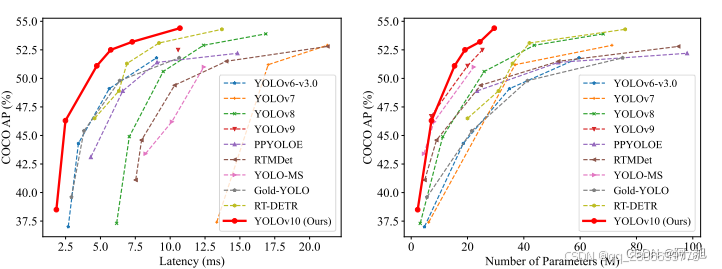

CT扫描图像的肾结石智能检测系统在医疗诊断方面提供了一种快速、准确的辅助工具,显著提高了医生识别和评估肾结石的效率。本文基于YOLOv10深度学习框架,通过1300张CT扫描的肾结石相关图片,训练了一个进行肾结石目标检测的模型,可以对CT扫描图像中的肾结石进行实时检测。并基于此模型开发了一款带UI界面的肾结石智能检测系统,更便于进行功能的展示。该系统是基于python与PyQT5开发的,支持图片、视频以及摄像头进行目标检测,并保存检测结果。本文提供了完整的Python代码和使用教程,给感兴趣的小伙伴参考学习,完整的代码资源文件获取方式见文末。

YOLOv;